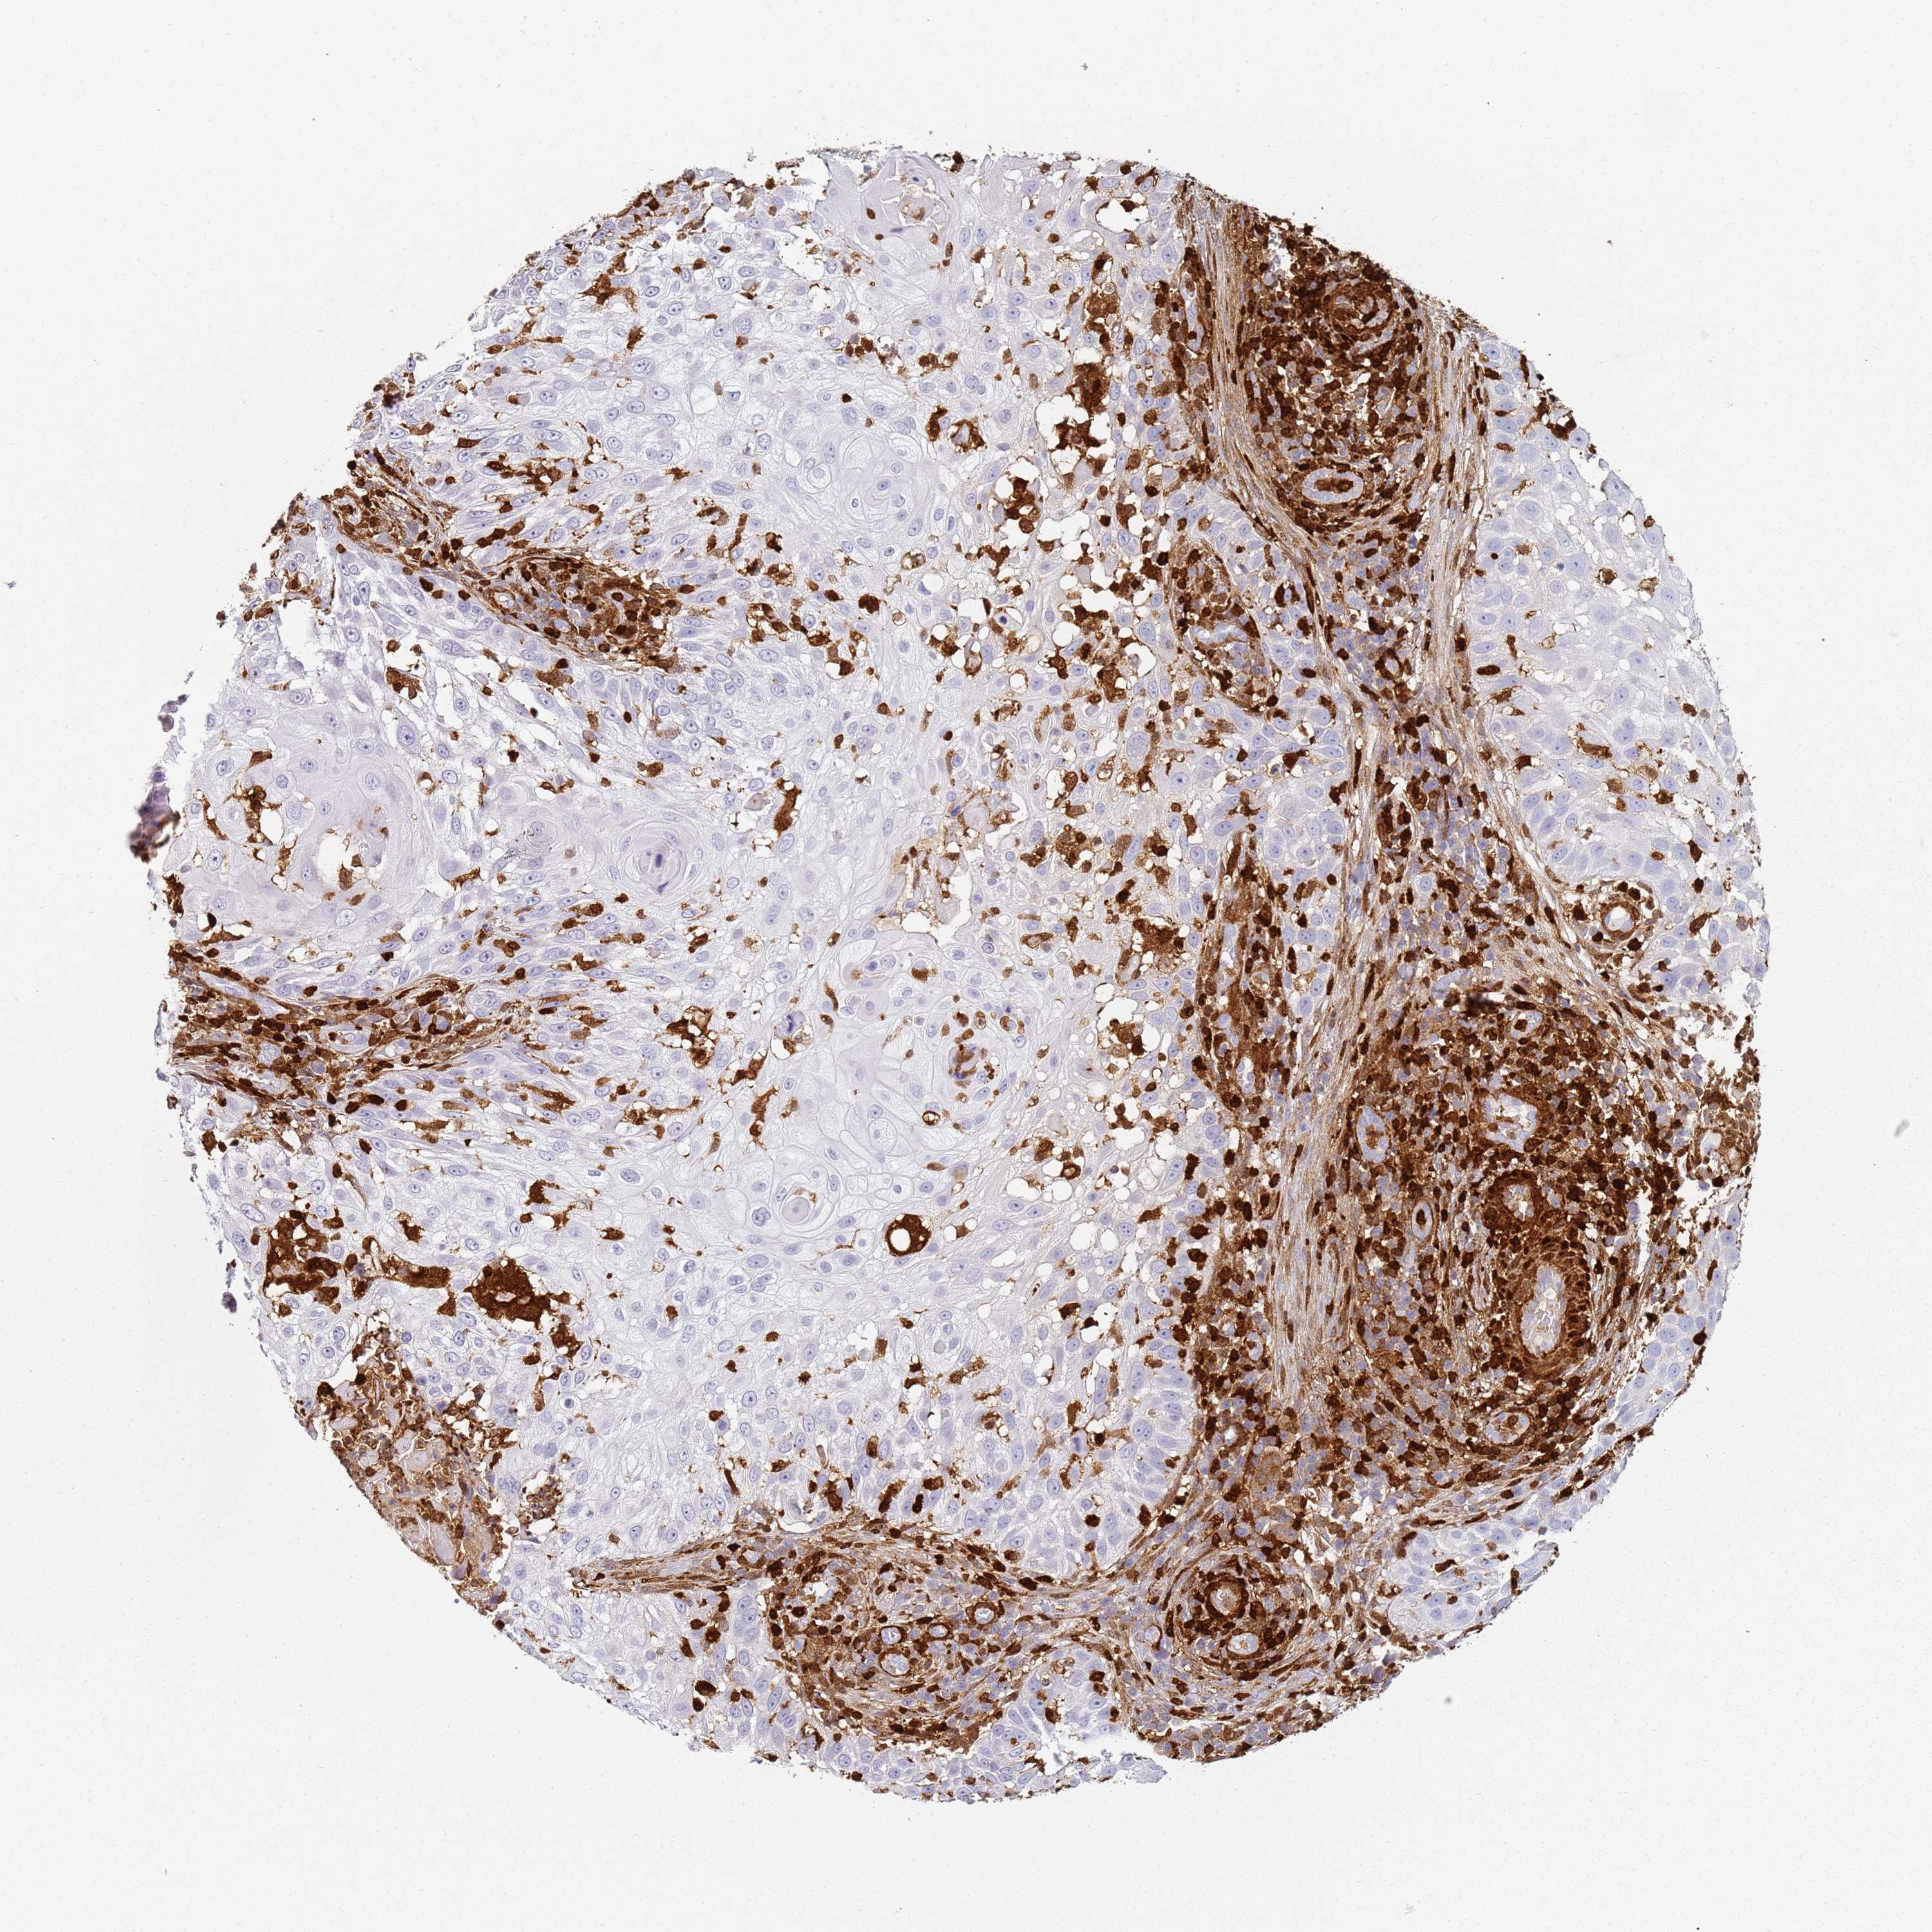

SKIN CANCER - Protein expressioni

A mouse-over function shows sample information and annotation data. Click on an image to view it in a full screen mode. Samples can be filtered based on level of antibody staining by selecting one or several of the following categories: high, medium, low and not detected. The assay and annotation is described here.

Antibody stainingi

Antibody staining in the annotated cell types in the current human tissue is reported as not detected, low, medium, or high, based on conventional immunohistochemistry profiling in selected tissues. This score is based on the combination of the staining intensity and fraction of stained cells.

Each image is clickable and will lead to virtual microscopy that enables deeper exploration of all samples and also displays staining intensity scores, fraction scores and subcellular localization as well as patient and tissue information for each sample.

Location

Nuclear

Cytoplasmic/membranous

Cytoplasmic/membranous,nuclear

None

Basal cell carcinoma

Squamous cell carcinoma, NOS

Squamous cell carcinoma, metastatic, NOS